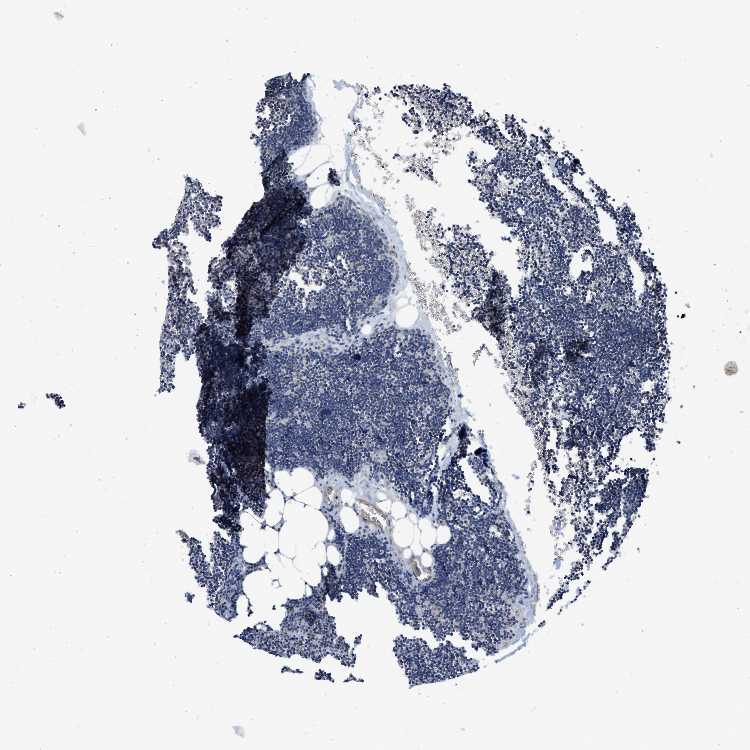

TISSUE PRIMARY DATA LYMPH NODE Show tissue menu

LYMPH NODE - Antibody stainingi

Antibody staining in the annotated cell types in the current human tissue is reported as not detected, low, medium, or high, based on conventional immunohistochemistry profiling in selected tissues. This score is based on the combination of the staining intensity and fraction of stained cells.

Each image is clickable and will lead to virtual microscopy that enables deeper exploration of all samples and also displays staining intensity scores, fraction scores and subcellular localization as well as patient and tissue information for each sample.

Antibody HPA003941Antibody CAB017040

Germinal center cells Not detectedNot detected

Non-germinal center cells Not detectedNot detected